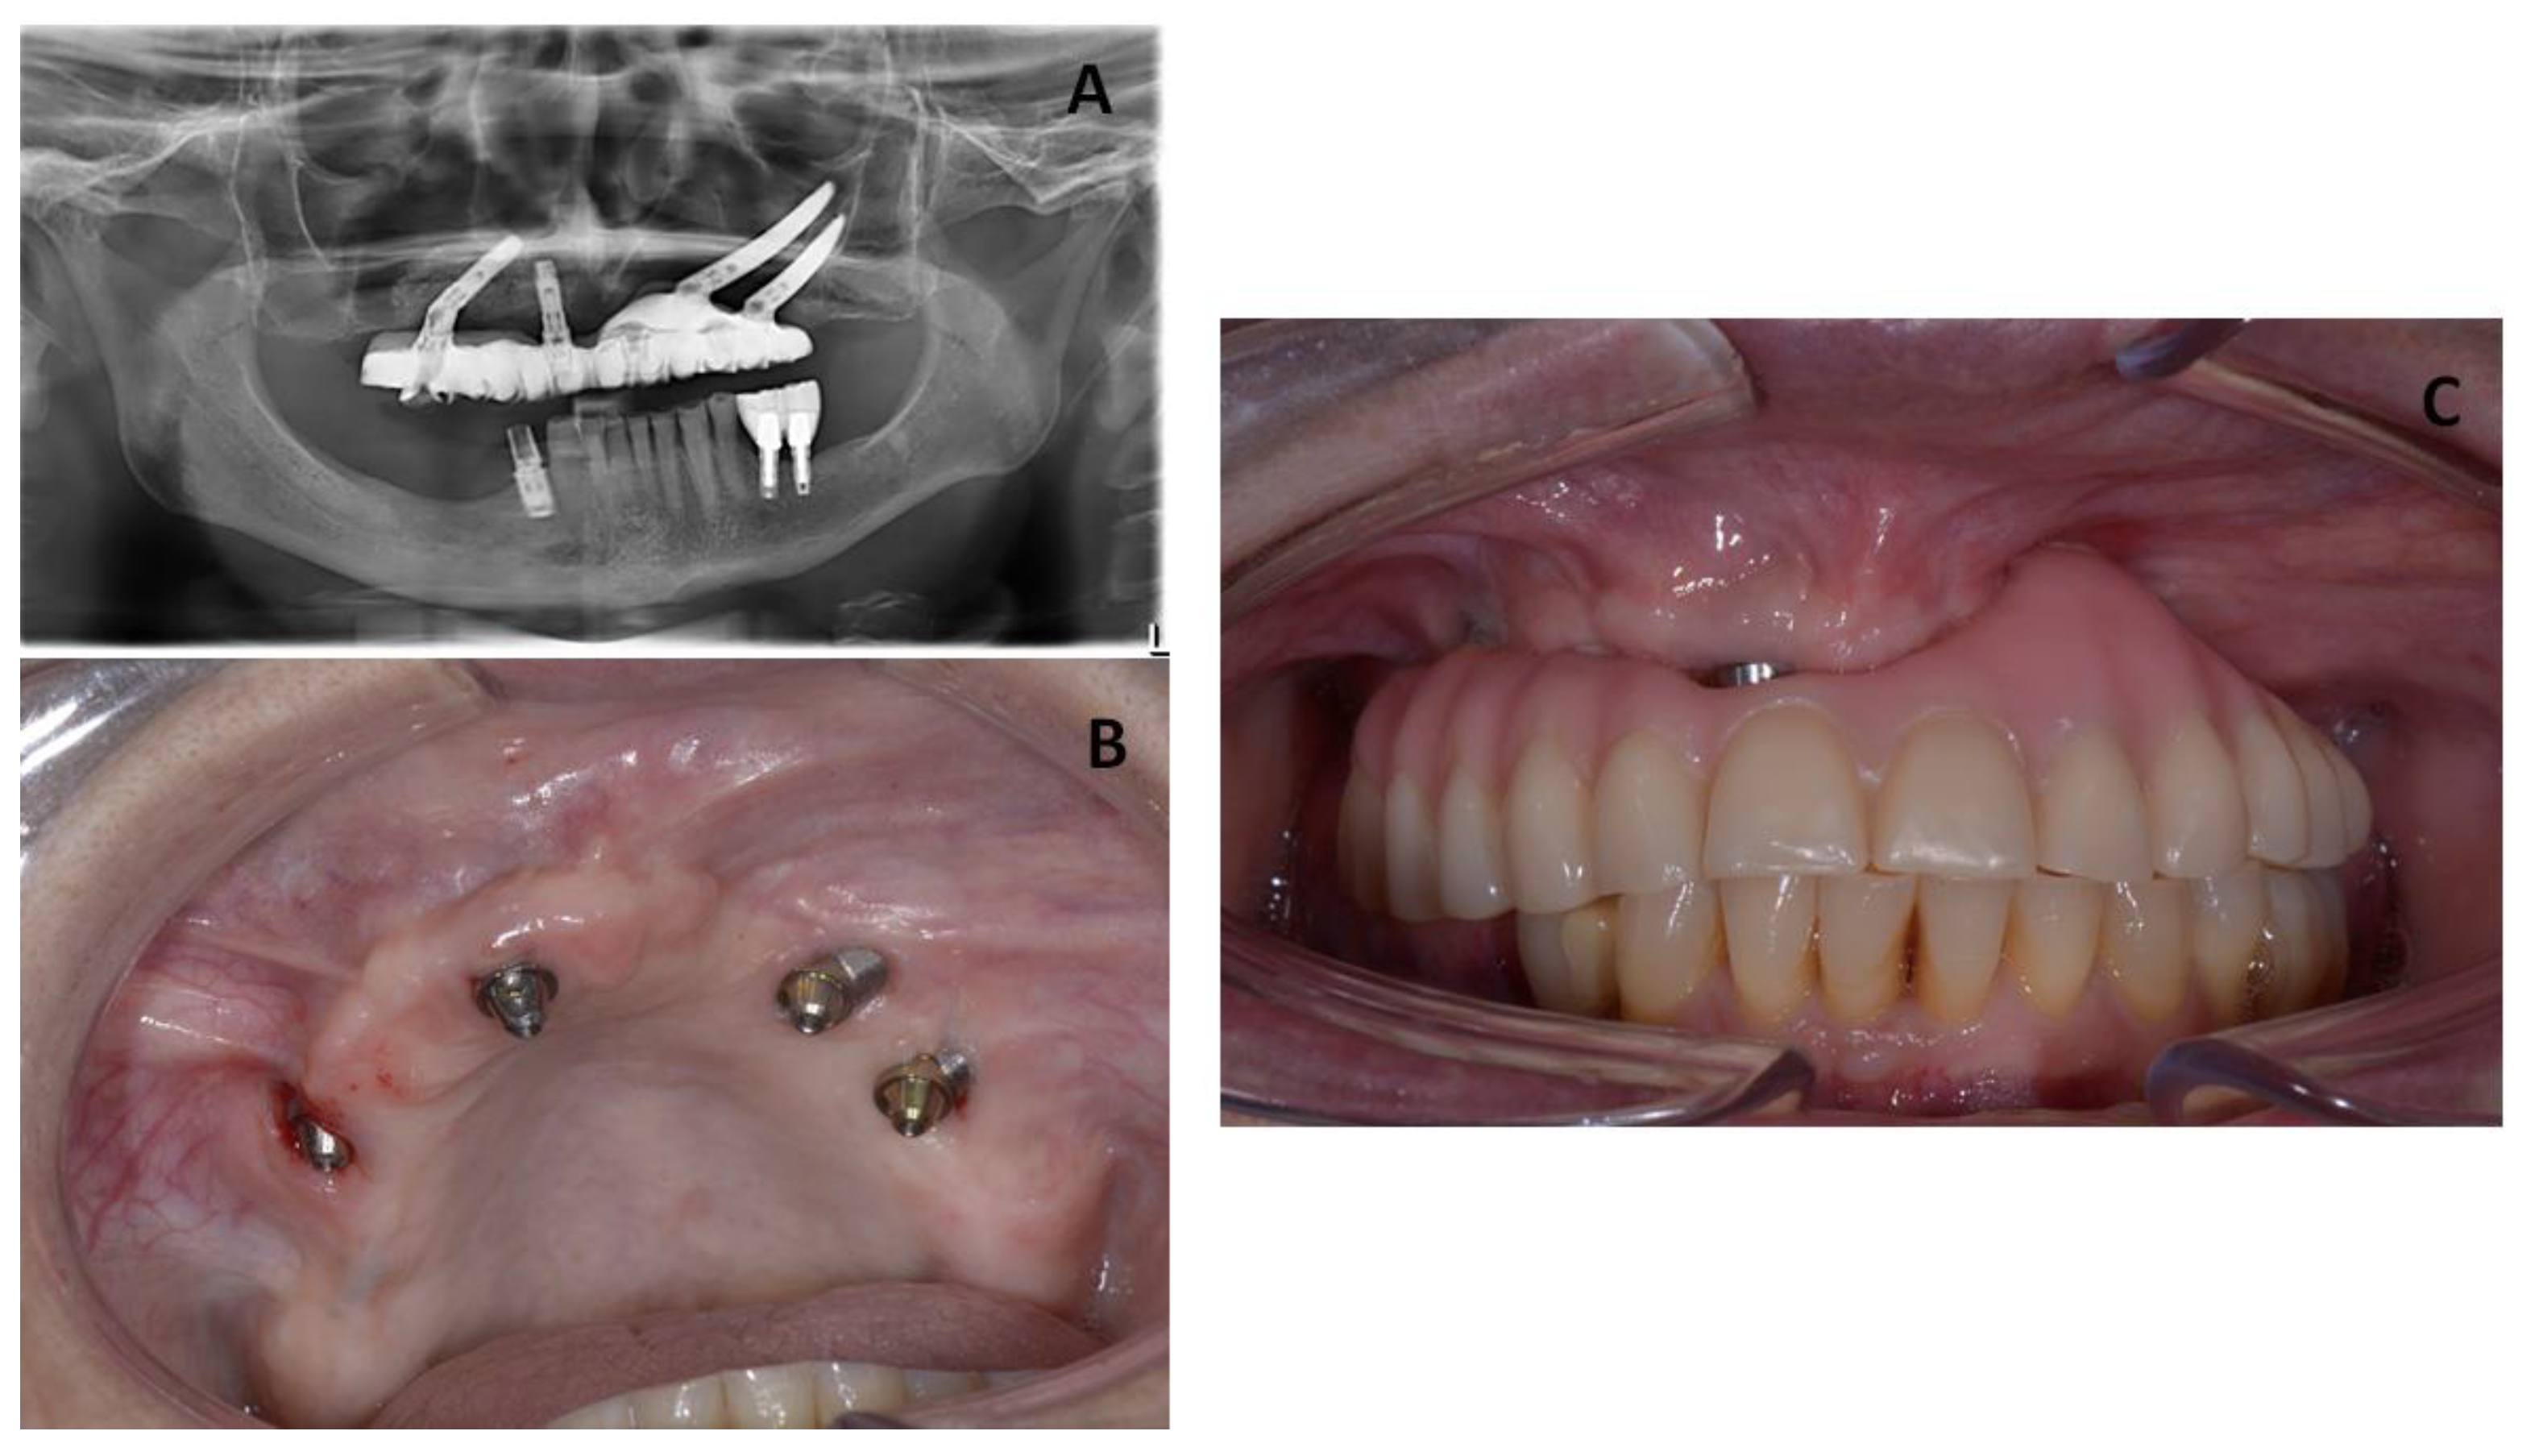

The patient was recalled for clinical follow-up every 3 months for the first year, and then twice a year. In these appointments, any changes or complications and any adverse events were evaluated, and the occlusion was examined carefully. Additionally, the Toronto prosthesis was unscrewed to check the status of the soft and hard tissues. Figure 6 presents clinical and radiographic images taken at 3 years of follow-up, showing healthy peri-implant tissues.

Figure 6. (A) Panoramic radiograph of the patient after 3 years of follow-up. (B) Clinical image from the patient showing occlusion.